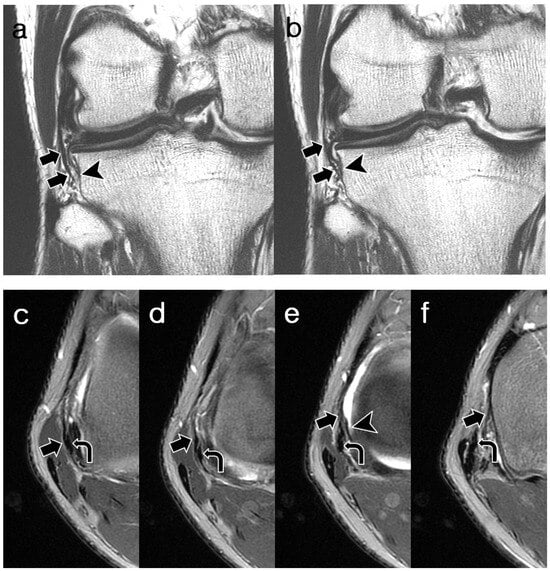

3.2. ALL Visibility

3.3. ALL Morphology